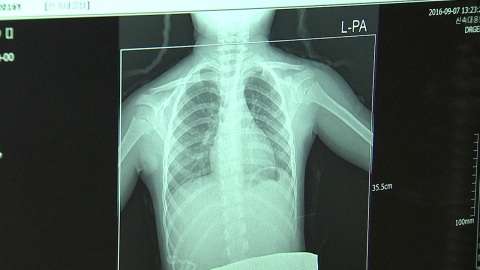

치료 거부하고 행방불명 결핵 환자, 전국에 113명

최근 4년간 결핵 진단을 받고도 치료를 거부해 행방불명 상태인 결핵 환자가 113명에 달하는 것으로 조사됐다.

조사에 따르면 지금까지 66명이 치료를 완료했거나 재개하였고, 9명이 사망했지만 아직 113명이 치료를 받지 않고 있는 것으로 확인됐다.

질병관리본부의 결핵 환자 관리현황에 따르면 주민등록지를 기준으로 인천 부평구 8명, 서울 강동·노원에 각각 6명, 서울 서대문구·금천구 4명, 서울 동대문·종로·영등포·구로, 인천 남동구, 경기 안산시단원, 전북 익산에 각 3명 등 총 113명의 결핵 환자가 치료를 받지 않고 행방불명된 상태다.